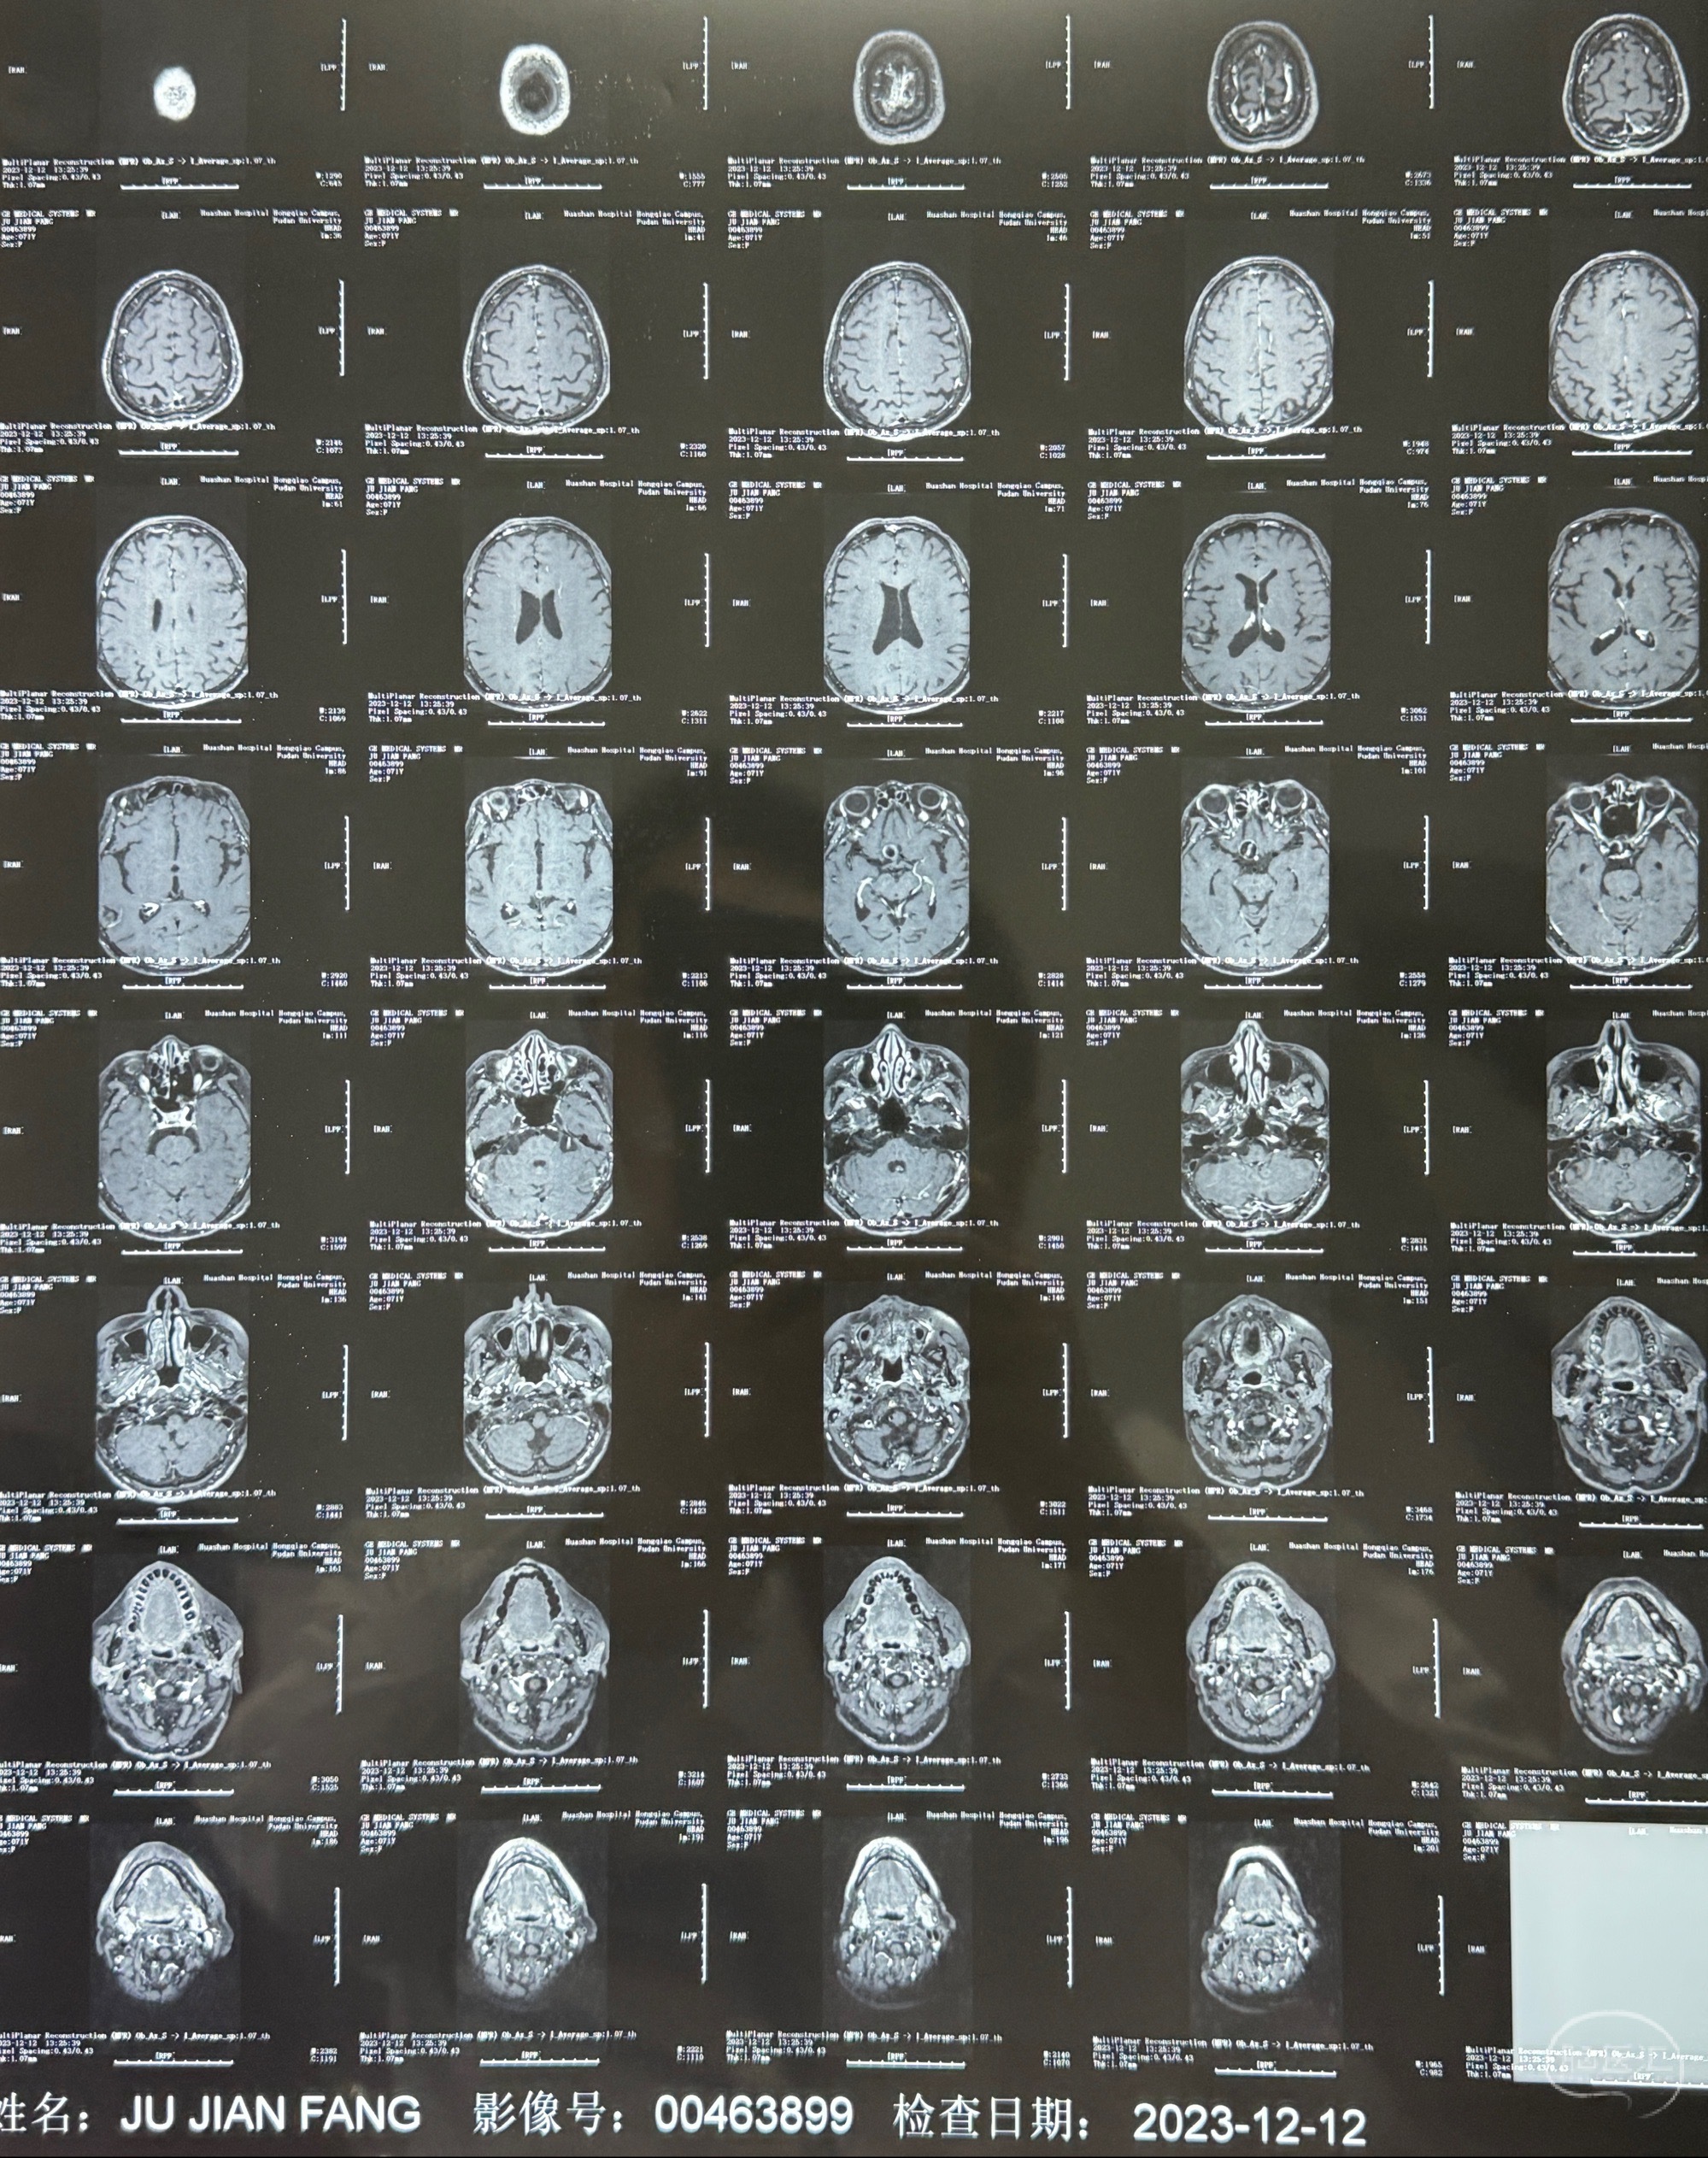

辅助检查;2023-11 外院 头颅MRI+MRA:左侧颈内动脉C6段动脉瘤;

2023-12-08 复旦大学附属华山医院 全脑血管造影:右侧颈内动脉C6段动脉瘤,瘤颈6.68mm,动脉瘤大小13.28*12.34mm

2023-12-12MRI